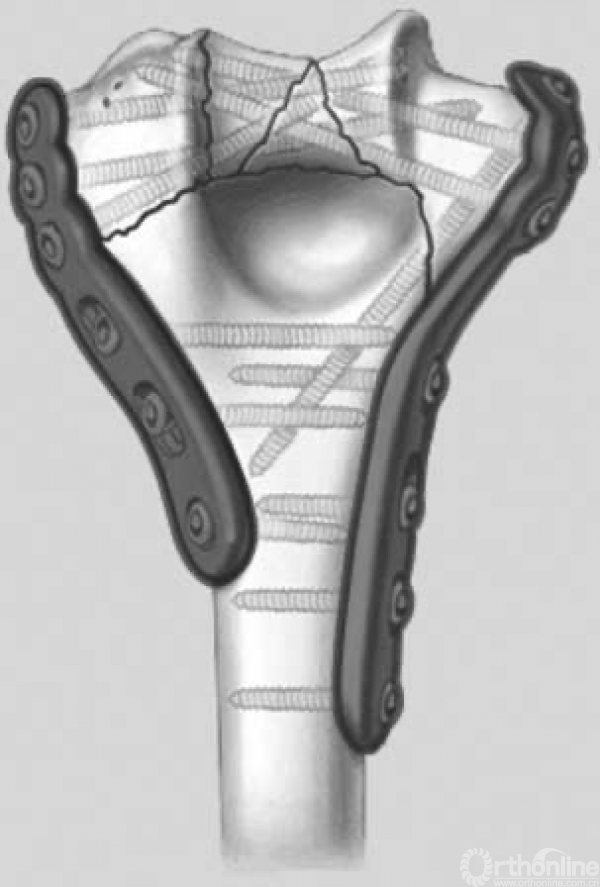

图1 技术目标1:远端骨折块的每颗螺钉都应经过钢板。

图2 技术目标2:远端骨折块的每颗螺钉都应穿过对侧骨折块

图3 技术目标3:在远端骨折块放置尽可能多的螺钉

图4 技术目标4:远端骨折块的每颗螺钉都尽可能要长

图5 技术目标5:远端骨折块的每颗螺钉尽可能多地连接每个骨折块

图6 技术目标6:远端骨折块的每个螺钉彼此交锁在一起,构造一种固定成角结构,进而形成拱形或闭环结构

图9 拱形结构刚性连接双柱的稳定性。这种拱形结构在插入基石之前是不稳定的,螺钉彼此交锁相当于在两个柱末端形成了拱形结构,内外侧柱上各自的坚固钢板通过这种拱形结构联结在一起,交叉螺钉相当于拱门的基石。这是由于这种结构的稳定性,粉碎性肱骨远端骨折或合并骨质疏松的患者能获得良好的内在稳定性。在插入“基石”,即放置彼此交锁的螺钉之前,这种结构是不稳定的。